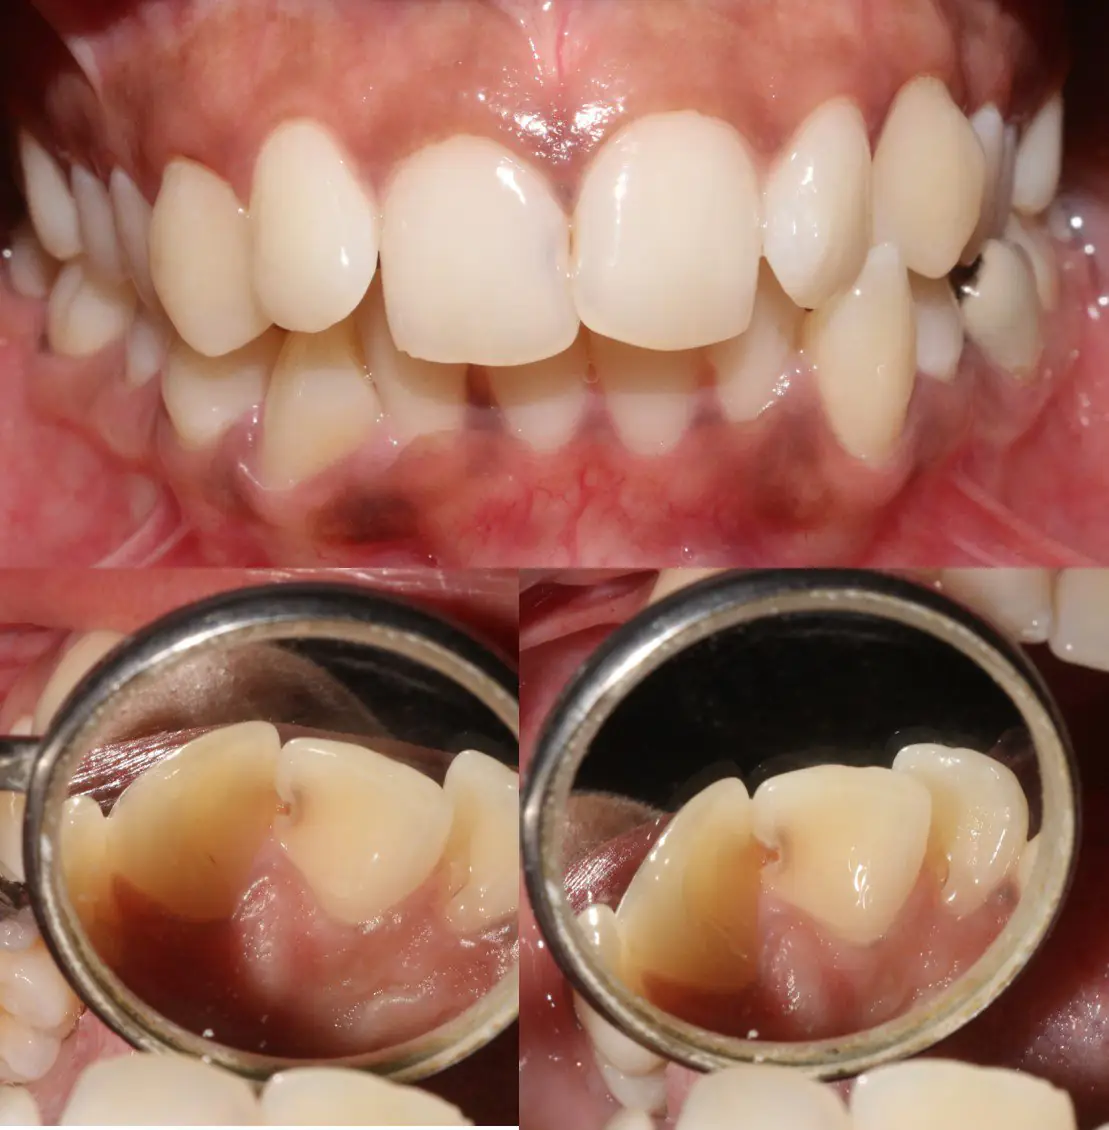

A 22 year old female presented to clinic complaining of decayed upper front tooth. On examination, class 3 carious lesion was noted on 11 and 21. Minor anterior crowding was also noted. (Fig:1 A-C)

Fig 1 A-C: A) Intraoral frontal view- class 3 caries irt 11 and 21 , Anterior crowding ;B and C) caries lesion from palatal view